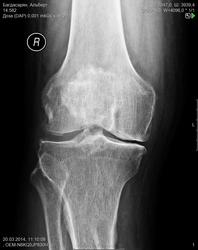

В принципе, можете про них вообще ничего не описывать. Суставная щель сужена, суставные поверхности раширены за счёт остеофитов, и всё )) отметьте обызвествления стенок сосудов. Гонартроз 2 ст.

Как бы IIIст. Выраженные краевые остеофиты.

2-я стрелка - это свободное суставное тело? А первая - обызвествление связки?

То что на суставной поверхности бедра (первая стрелка) - остеофит, вы их описываете фразой "суставные поверхности расширены за счёт остеофитов" или как вам больше нравится. По поводу второй стрелки мнения разошлись, но я бы ничего не писал про нее.

Слева направо 1 стрелка - остеофит суставной поверхности бедра, 2 стрелка - сесамовидная кость fabella, 3 - кожная складка.

Всё-таки вторая стрелка не фабелла, остеофит или хондромное тело.

Окостенение связки, тендиноз

кальцифицирующий склероз Менкеберга